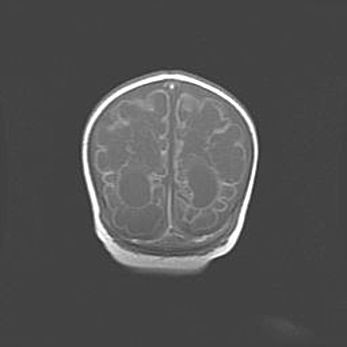

Наружная гидроцефалия с возможной атрофией височных областей.

Возраст: 28 дней

Вес: 3670 г

Пол: мужской

Окружность головы: 38 см

Срок гестации: 40 недель

Гидроцефалия головного мозга у новорожденных – это заболевание, которое характеризуется скоплением избыточного количества спинномозговой жидкости в желудочковой системе головного мозга в результате затруднения её перемещения от места выработки к месту поглощения в кровеносную систему или вследствие нарушения абсорбции. При открытой наружной форме гидроцефалии у новорожденных расширяются и переполняются субарахноидные пространства.

При нормотензивных  формах,  которые,  как  правило,  являются  следствием  перенесенных ишемических  повреждений  паренхимы  мозга,  возможно  сочетание микроцефалии  с нормотензивной гидроцефалией. В основе данных изменений лежит атрофия больших полушарий с преимущественной  локализацией  в  лобно-височных  областях.